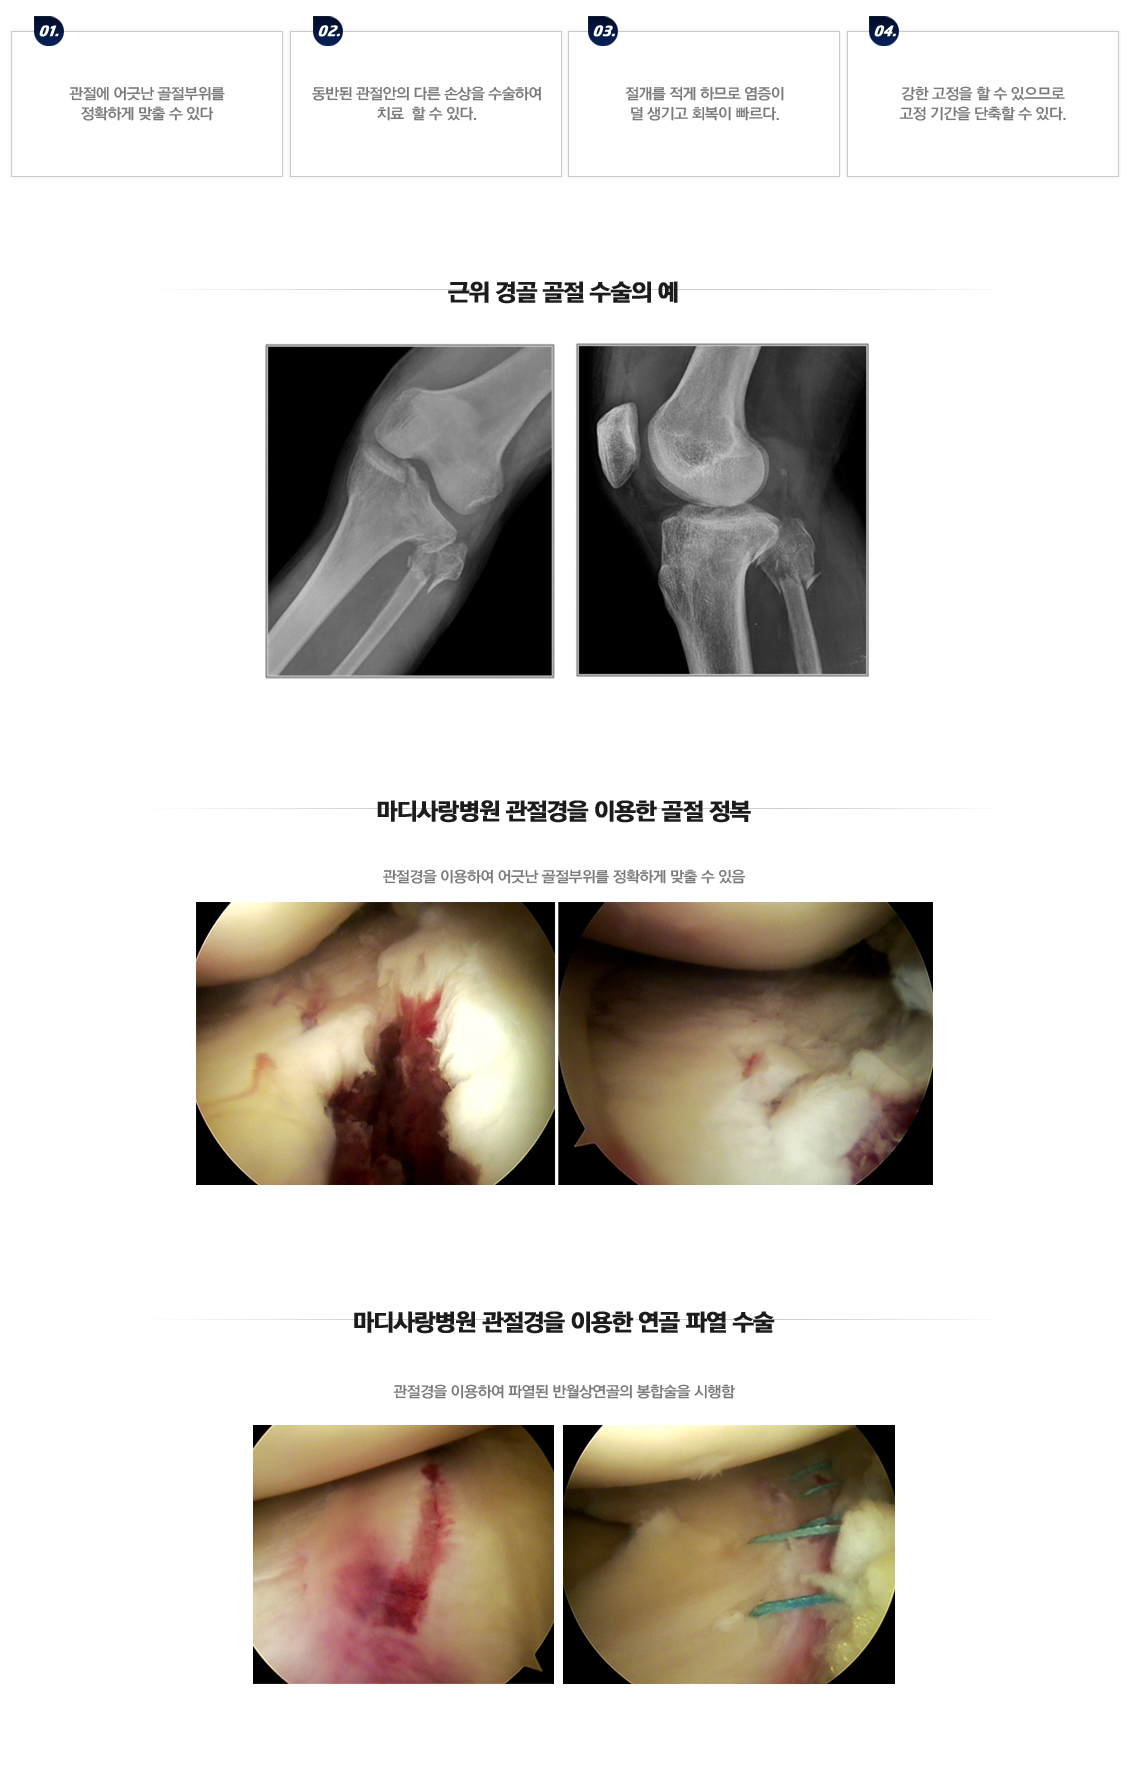

무릎골절

근위경골 절골술

무릎 골절수술